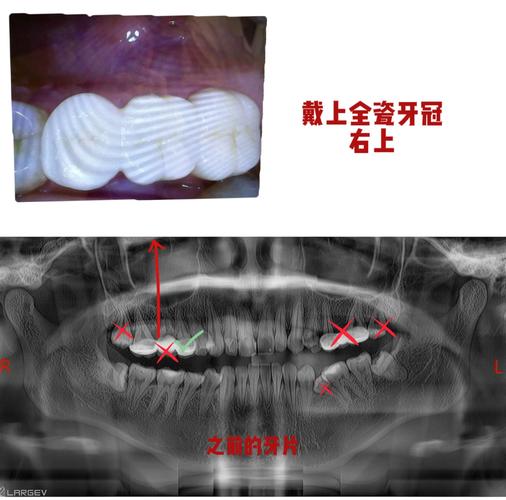

- 技师工作: 技师会根据模型选择合适的材料(如全瓷、金属烤瓷、全锆等),在模型上制作牙冠,确保其形态、颜色、大小与邻牙高度协调,咬合关系正确。

(图片来源网络,侵删)- 目的: 在永久牙冠制作完成后,医生会先让您试戴,检查牙冠是否合适。